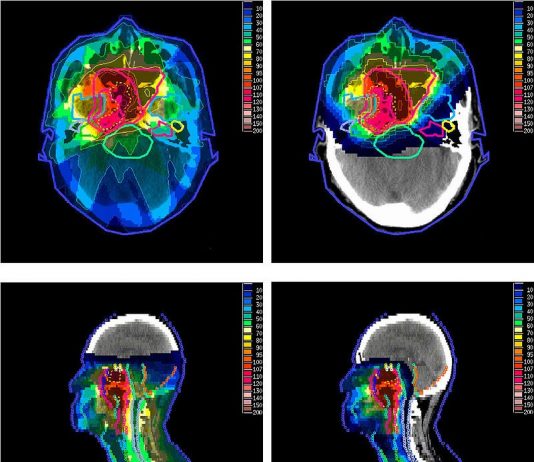

What Is Proton Therapy?

Proton therapy or proton beam therapy is a type of particle therapy that uses a beam of protons to irradiate diseased tissue, most often in the treatment of cancer. The chief advantage of proton therapy over other types of external beam radiotherapy is that...